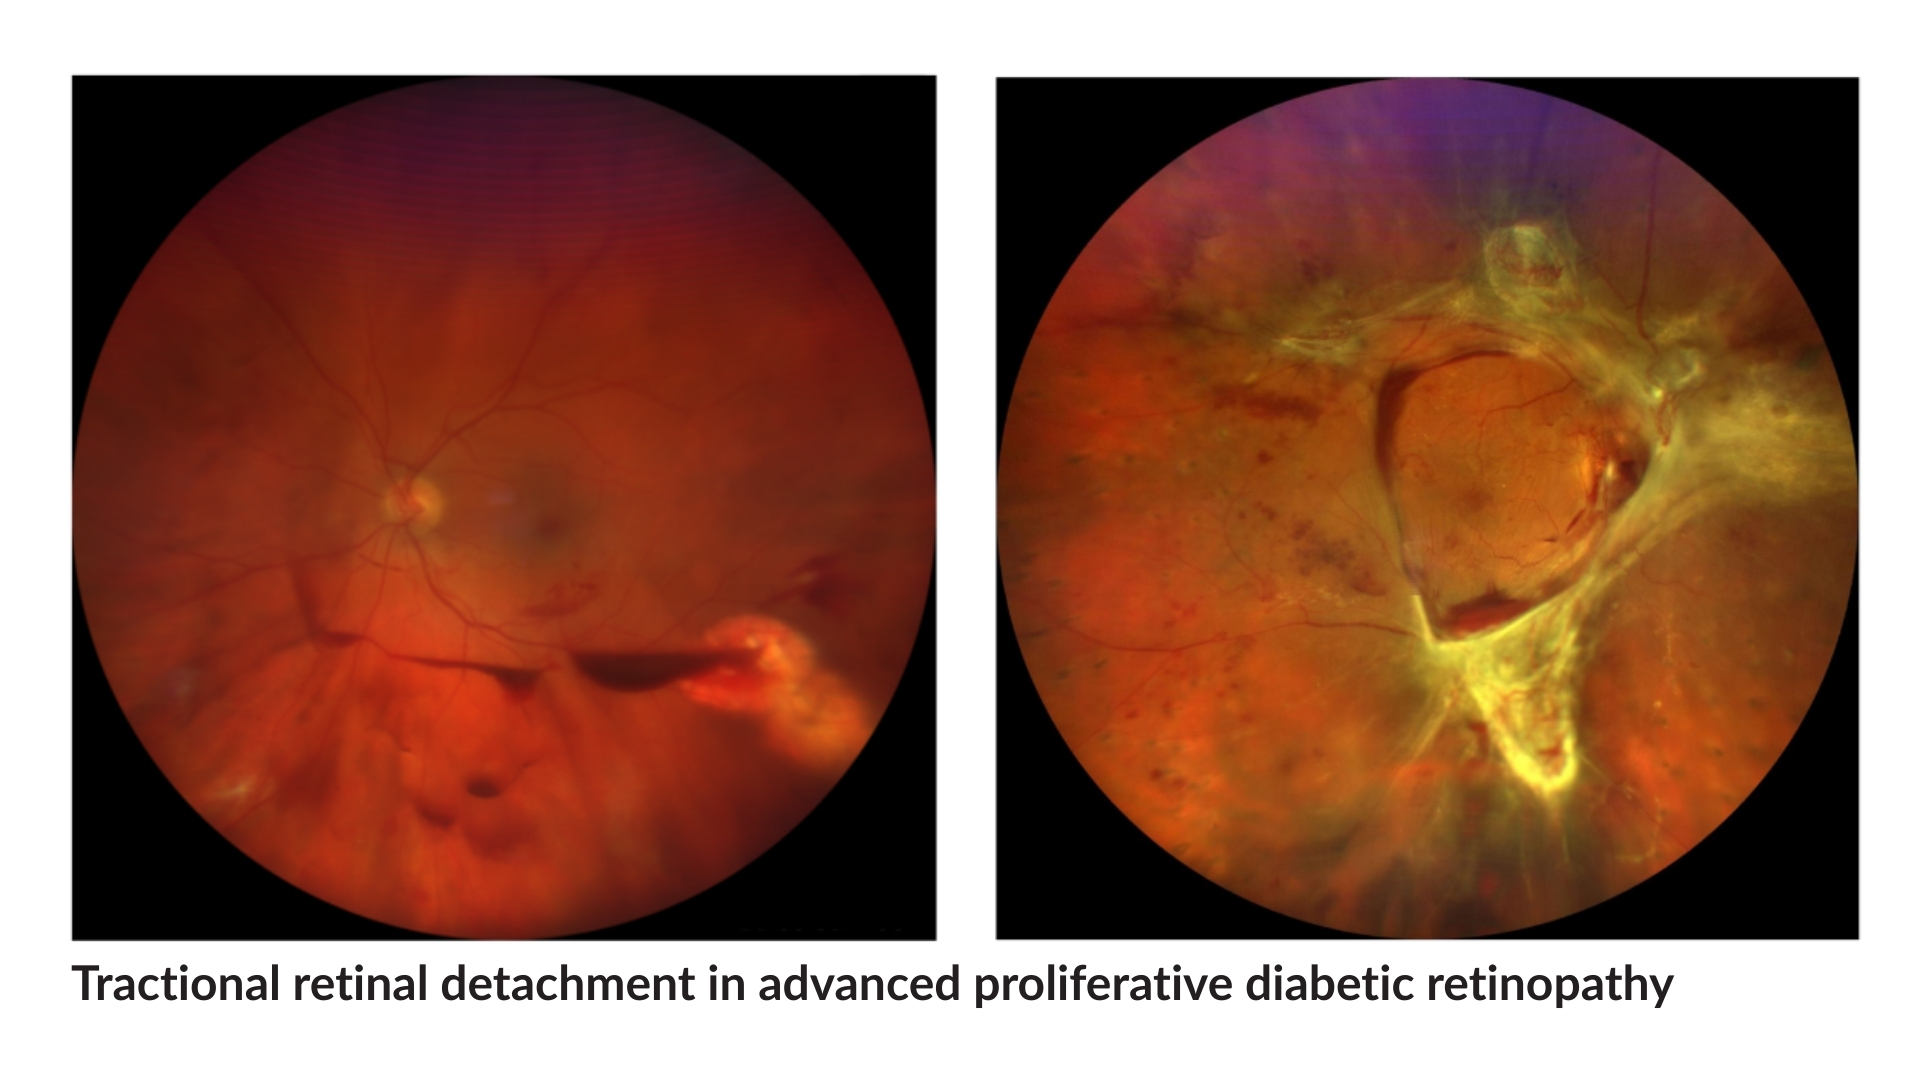

Diagnostic Assessment of Diabetic Retinopathy

In order to guide the most appropriate treatment, precision diagnostic assessment is essential. For diabetic retinopathy, the following diagnostic tools assist in determining optimal disease management:

- Ultra Wide-field Fundus Photography

- Spectral Domain OCT

- Fluorescein Angiography

- OCT Angiography

As diabetic retinopathy is a long-term condition, regular post-treatment follow-up is required. Monitoring will involve consultation visits, where diagnostic testing such as macular OCT, fluorescein or OCT angiography, and Wide Field Fundus imaging will be performed to precisely assess your diabetic retinopathy status. Regular monitoring allows any further changes such as leakage or bleeding to be addressed appropriately, in order to protect vision over time.

12. What tests are usually repeated during follow up visits?

Follow up may include OCT, retinal imaging, or angiography to monitor retinal swelling and blood vessel changes.